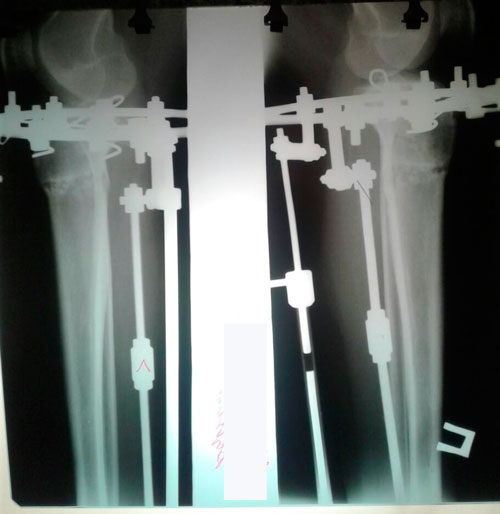

Дата операции 06.07.2017г.

Дата снятия аппаратов 05.10.2017г.

Срок лечения 90 дней.

Наталья, можете выложить сюда последний рентген? 90 дней